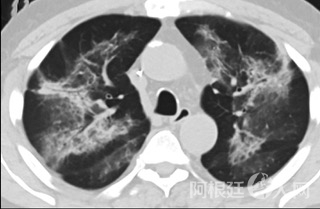

疑点二,中国科研工作者从60篇研究论文中筛选出142位电子烟肺炎患者的250张影像图片,邀请3位放射科权威专家,对上述全部影像图片、相关病人临床信息以及文献原文进行了仔细全面研究与审查,又有了新的发现。

6天后的轴向CT平扫图像显示毛玻璃影变为实变和轻度结构扭曲。(同一病人CT影像)

16位被文献报道为电子烟肺炎的患者被专家判定为“病毒性感染”,即有可能是新冠肺炎的“疑诊患者”,其中更有5位临床症状和治疗情况相对完整的患者被判定为“中度可疑”。因此在2019年美国报道的电子烟肺炎中存在病毒性感染的病例,而且不排除美国电子烟肺炎中存在新冠肺炎的可能性。